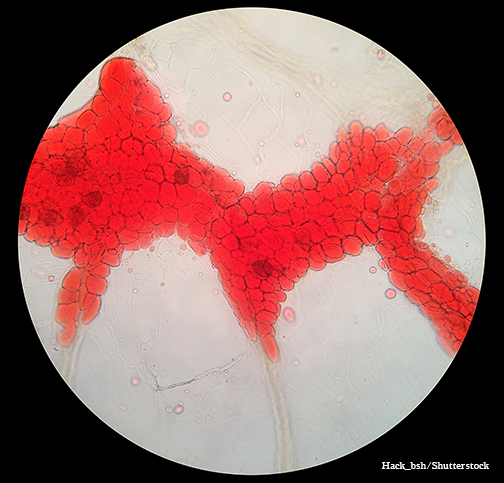

LSU Health Research Finds New Drug Target for Triple-Negative Breast Cancer

Research led by Dr. Suresh Alahari, Professor of Biochemistry at LSU Health New Orleans’ Schools of Medicine and Graduate Studies, reports a combination of a novel small inhibitory molecule and an FDA-approved chemotherapy drug suppresses the growth of triple-negative breast cancer cells synergistically. More

Study Reports Blocking Key Enzyme Boosts Anti-Cancer T-Cell Responses and Resistance to Immunosuppression

A study led by LSU Health New Orleans cancer researchers describes a novel therapeutic strategy to overcome tumor-induced immunosuppression. For the first time, the research team identified a critical immunosuppressive pathway and a promising approach to intervene, protecting the ability of T-cells to attack cancer cells. Results are published in Frontiers in Immunology. More

LSU Health Research Suggests Novel Combination Therapy for Triple-Negative Breast Cancer

Research led by Suresh Alahari, PhD, Professor of Biochemistry at LSU Health New Orleans schools of Medicine and Graduate Studies, suggests a combination of drugs already approved by the FDA for other cancers may be effective in treating chemo-resistant triple-negative breast cancer. More